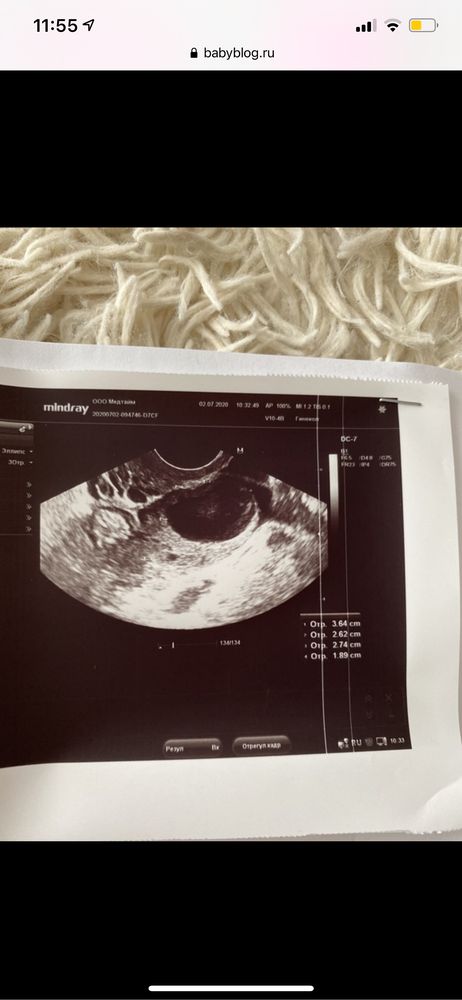

вот такой был

У меня такая была.